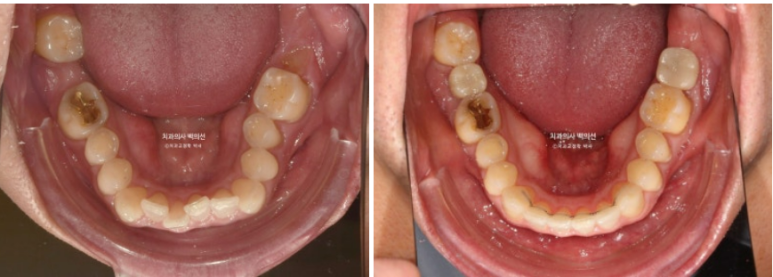

사진에 듬성듬성 보이는 총 3군데의 빈공간은 어금니가 없는 상태입니다.

언젠가는 임플란트를 해야지 하고 없는 채로 시간이 흘러 주변 어금니들이 빈공간으로 쓰러진 상태입니다.

쓰러진 큰어금니를 세워 좁아진 임플란트 공간을 2mm 가량 더 확보했습니다.

배열도 개선이 많이 되었습니다.

처음보다 많이 좋아졌지만 임플란트 공간을 좀 더 확보하고 배열의 완성도를 높이고자 재제작에 들어갑니다.